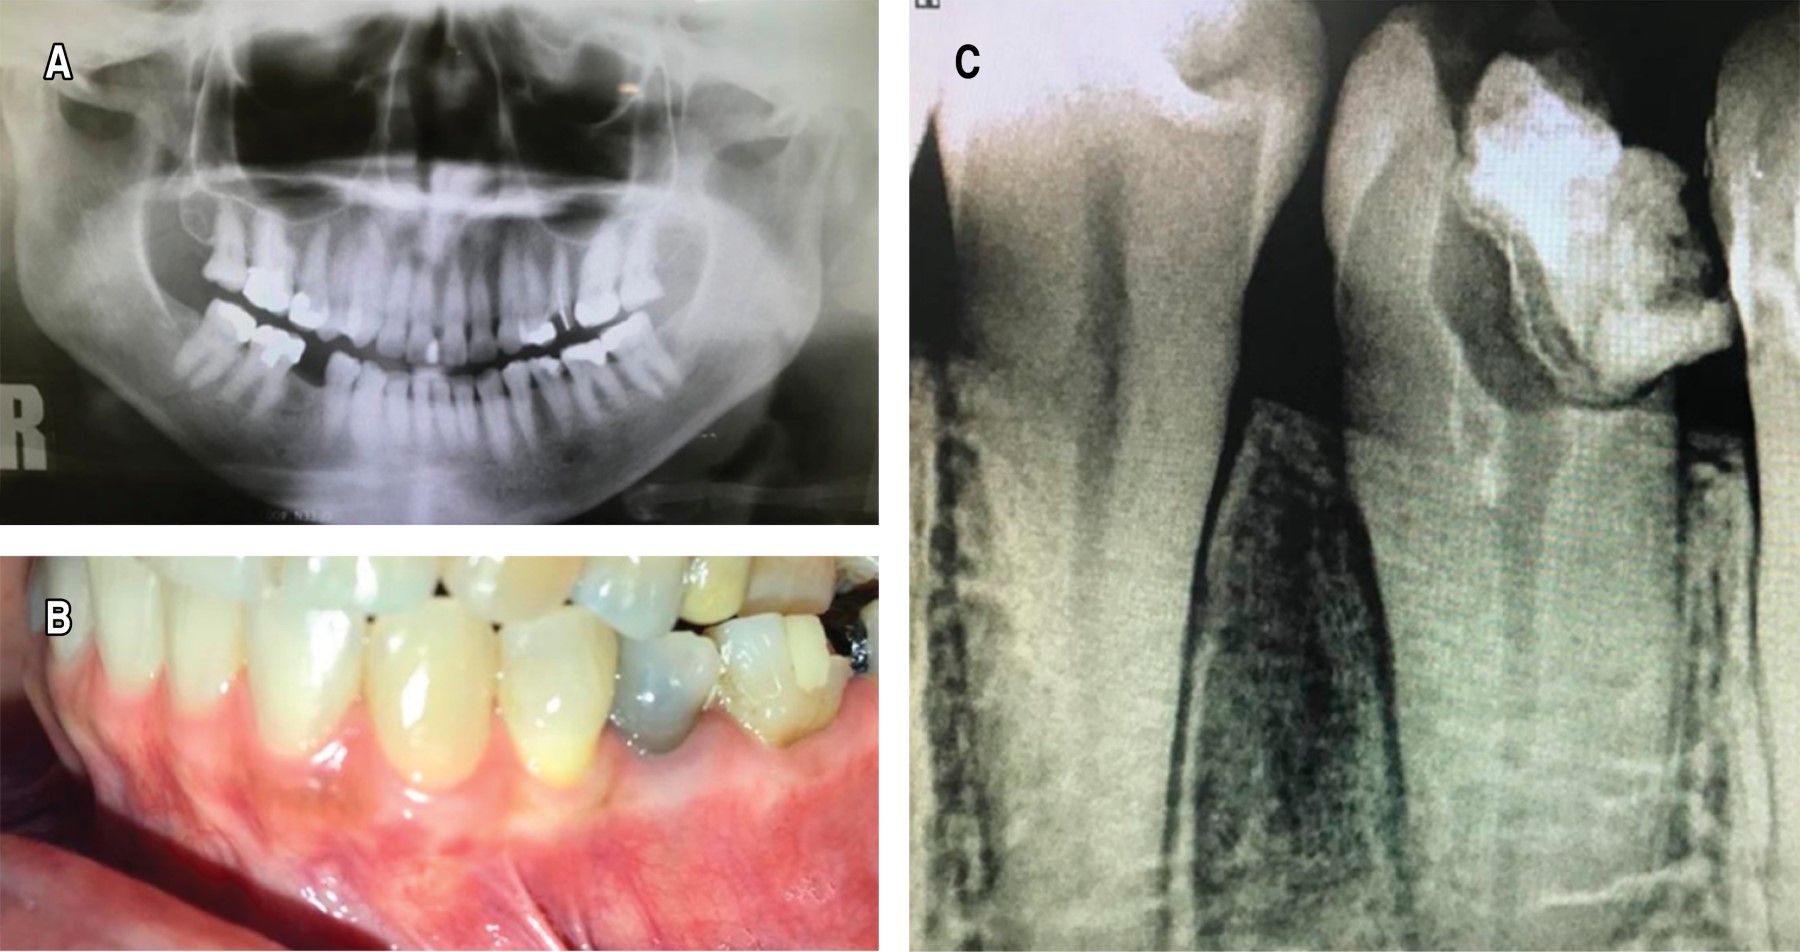

Al examen imagenológico se evaluó una radiografía panorámica dental sinusal, donde se observa una imagen radiolúcida de bordes definidos ubicado entre órganos dentarios 3.4 y 3.5, que abarca de la porción ósea crestal a tercio medio inferior radicular, sugerente a pérdida de estructura ósea. De igual forma se evaluó una tomografía de haz cónico mandibular, donde se observó imagen hipodensa en contraste con densidad de estructura ósea, de 8.08 mm de altura por 2.48 mm de ancho en su porción más cefálica y 4.03 mm de ancho en su zona más caudal × 6.43 mm de profundidad, se observa solución de continuidad de cortical vestibular, se observó cortical lingual sin alteraciones (Figura 2).

Figura 2